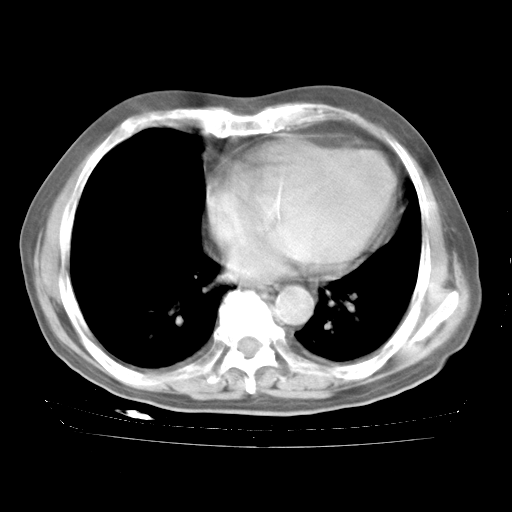

4月28日肺部CT——再次出现类似去年5月9日——透光度降低,“间质性”改变。

4月28日肺部CT——再次出现类似去年5月9日——磨玻璃样、间有“粟粒样”改变。

4月28日肺部CT

个人阅读4.14日肺部CT平扫:纵隔窗无异常,但肺窗示:双下肺内、后基底段有片絮状侵润影,部位以后基底段为著,以间质改变为主,呈急性肺泡炎征像,和首次住院影像学有相似之处。仅是个人读片,明日请相关专家再读片哈。其它建议同上。

1、108#的是4月14日的胸部CT(发此贴时还没看着28日的CT)。14日的胸部CT其实已经出现改变(如108#所述),个人认为28日的胸部CT除纵膈窗疑似有双侧胸膜增厚或少量胸积液(可行胸部B超明确)外,与4月14日对照病变有所加重;2、已经给予“异烟肼、利福平、乙胺丁醇”抗痨治疗?如果是,甲强龙80mg可缓慢减量;如果环磷酰胺已停用,暂不使用;3、中性粒细胞92%,明显升高,目前体温情况?注意合并细菌感染可能,使用左氧氟沙星情况下,是否联用B-内酰胺类抗菌药物?另外是查免疫全套非风湿全套。

今请临免主任会诊后认为:4月14日胸部CT已有双下肺间质性改变。患者病情复发多系激素减量过快不正规所致。目前甲强龙80mg/日,一周后酌情开始减量,不易过快。环磷酰胺若已停用,暂不使用。他同意目前抗菌药物使用,但应考虑是否加用B-内酰胺类抗菌药物(中性细胞明显增高);2、结核复发目前依据不足;3、若免疫全套各项指标正常,考虑多系特发性肺间质炎可能大。4、加强支持,并注意保护胃黏膜。

今上午去请教了临免、呼吸主任:1、介绍病史和阅读系列胸部CT一致认为:患者肺结核不考虑,仍为肺间质纤维化,目前处于急性肺泡炎阶段。2、若仍发热,可将甲强龙增至:80mg Bid静滴,同时鉴于中性增高,合并细菌感染可能,继续左氧氟沙星治疗,再联用B-内酰胺抗菌药物,如头孢哌酮--舒巴坦;3、停用抗痨药;4、目前甲强龙每日剂量160mg ,体温正常后再酌情减量;目前暂不用免疫抑制剂;4、不建议使用免疫增强剂等;5、加强支持治疗,鼓励患者进食;5、注意随访肝、肾功及血常规情况;6、因患者目前激素用量较大,加用胃黏膜保护剂,防止消化道出血可能。